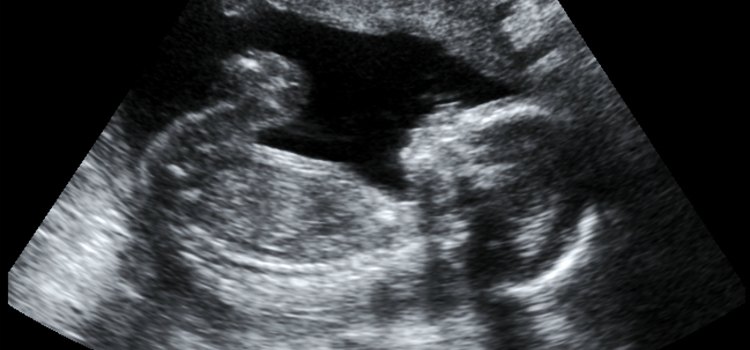

Estas la consolaron y hablaron con ella y le pidieron que pensara mejor sobre la elección. Tenía derecho a pedir una ecografía para ver cómo estaba el feto. Fue eso lo que estas mujeres le aconsejaron que hiciera.

Después de mucha insistencia en el hospital, Jill, finalmente, se realizó la prueba. Lo que vio la conmovió por completo, lo que hizo que su forma de pensar cambiase. Esta notó que una persona pequeña se formaba dentro de ella y comenzó a amarla de inmediato. Entonces, Jill decidió no abortar, a pesar de los temores y de no saber cómo iba a criar a su pequeño.